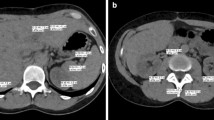

Quantitative evaluation of enhancement

Images of single-syringe power-injector protocol and double-syringe power-injector protocol were loaded on a workstation (MagicView 1100, Siemens, Erlangen, Germany) and viewed side by side on two monitors in random order. Monitor setting did not show patient data; consequently, the observer was blinded to the study date and thus to the power injector used. Loading processes and measurements were performed by different authors. Region of interest (ROI) measurements were performed for both protocols on corresponding slices in liver, spleen, pancreas, renal cortex, portal vein, inferior vena cava, and abdominal aorta aligned to anatomical landmarks to obtain mean contrast enhancement. The ROI settings in parenchymal organs were placed in areas without pathologic lesions that showed visually homogenous contrast material enhancement with exclusion of visible blood vessels. An attempt was made to maintain a constant ROI of approximately 1–2 cm2 in parenchymal organs and an ROI including nearly the whole vessel diameter, respectively. Table 1 shows the number of ROIs and the locations of ROI setting for the parenchymal organs and the vessels.

In 2 patients the liver was not measured because of fatty infiltration, which was defined as visually less enhancement of the liver compared with the enhancement of the spleen. In an additional 2 patients the spleen was not measured because of splenectomy, and in 4 patients the pancreas was not measured because of pancreatitis. The renal cortex, the portal vein, the inferior vena cava, and the aorta were measured in all patients.

There was no significant difference in mean enhancement along the z-axis for the parenchymal organs for both protocols. With the single-syringe power-injector protocol, the mean enhancement of the superior liver segments was 106±12 HU, of the inferior liver segments 105±11 HU (p=0.123). The corresponding enhancement values were 105±12 and 106±12 HU for the superior and inferior pole of the spleen (p=0.199) and 150±27 and 151±26 HU for the superior and inferior pole of the kidneys (p=0.451). With the double-syringe power-injector protocol, the corresponding enhancement values were 114±15 and 113±13 HU for the liver (p=0.128), 112±13 and 114±15 HU for the spleen (0.120), and 159±26 and 160±31 HU for the kidneys (p=0.316; Fig. 2).

Mean enhancement (mean±SD) of the superior pole (s) and inferior pole (i) of the liver, spleen and renal cortex for single-syringe power injector (triangles) and double-syringe power injector (squares). Note that there is no statistically significant difference in mean enhancement between superior and inferior pole of the organs (p<0.05)